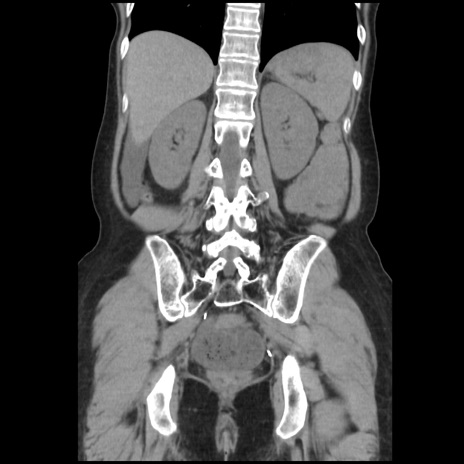

症例32(冠状断像)

【症例】40歳代 女性

【主訴】上腹部痛、嘔気・嘔吐

【現病歴】約9時間前頃から急に上腹部痛、嘔気、嘔吐が出現。改善しないため救急要請。

【既往歴】子宮頚癌(広汎子宮全摘術、放射線療法)、腸閉塞

【身体所見】腹部:平坦、軟、腸雑音亢進、上腹部を中心に腹部全体に圧痛あり。

【データ】WBC 8400、CRP 0.03